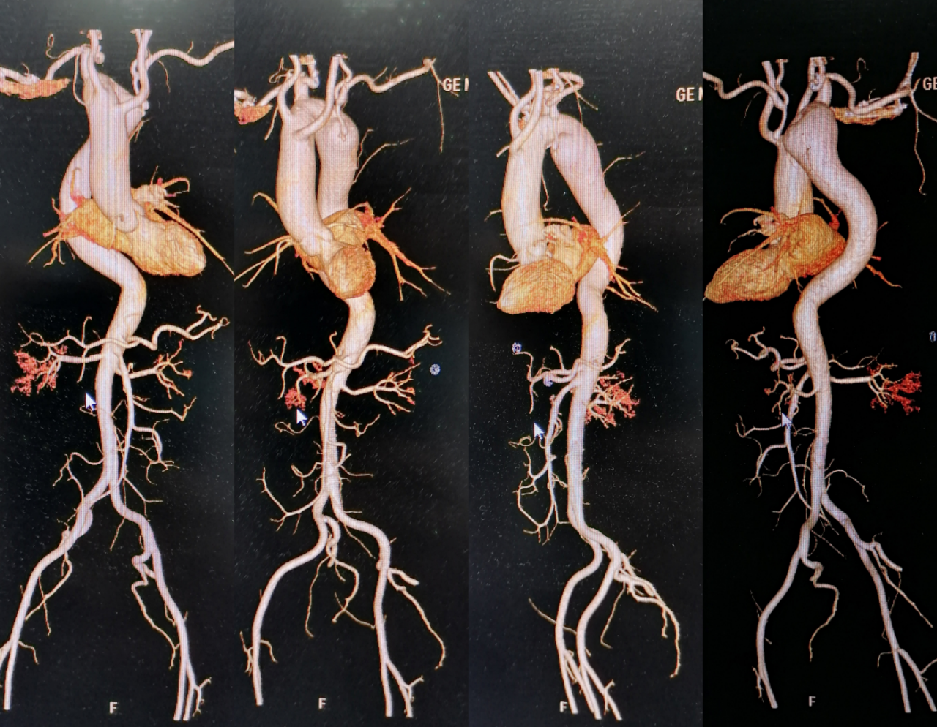

★Case 3 主动脉破裂+右位弓+ 迷走左锁骨下动脉+ Kommerell憩室

治疗难点:主动脉濒临破裂、解剖复杂

手术策略:Castor支架迅速封堵破口+潜望镜技术重建双侧锁骨下动脉

结果:快速稳定血流,患者转危为安

术后一月复查CTA,Castor支架及潜望镜通畅,假腔隔绝良好,纵膈及胸腔血肿吸收。

术后一年复查CTA,潜望镜远端出现Ib型内漏